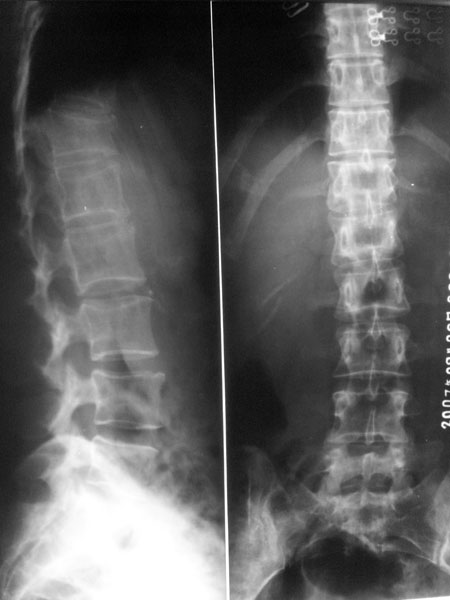

车祸致t12压缩性骨折,行ct扫描意外发现椎体多发肿瘤样病变,建议加拍骨盆平片,患者平常无症状。

椎体多发性溶骨性破坏,部分融合,椎旁无软组织肿块、椎间隙正常,t12 压缩,脾脏增大,其内示多发低密度影,首先考虑多发性骨髓瘤。病人较年轻,平素无异常,转移瘤可能性小。